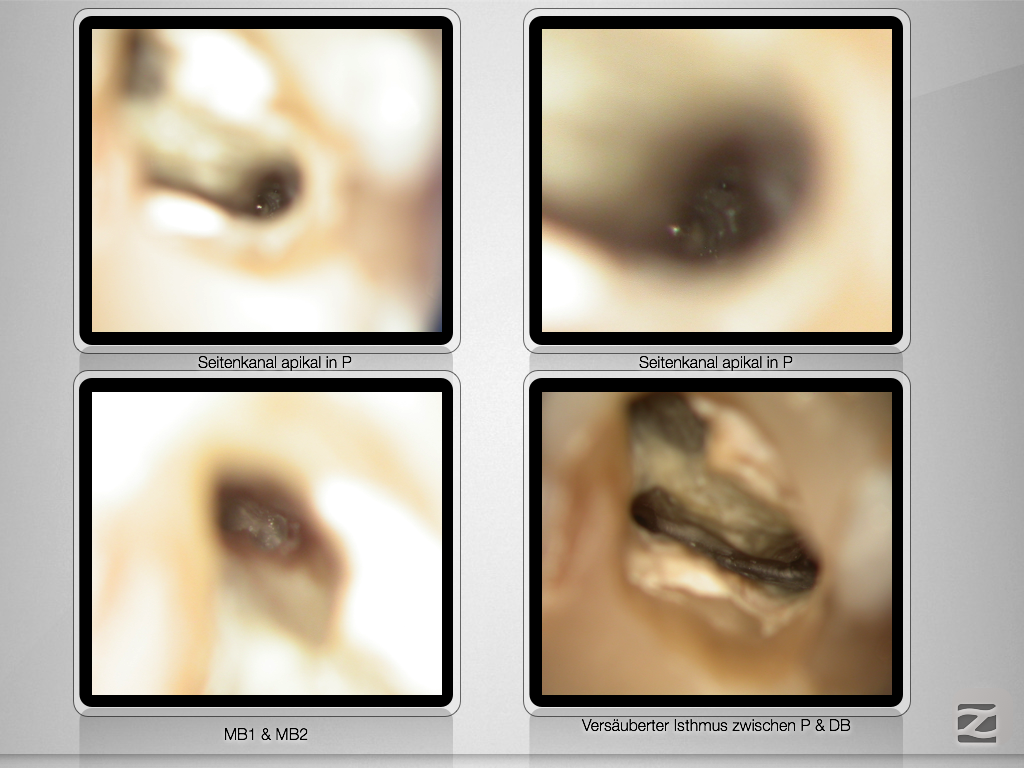

Navigierte Aufbereitung